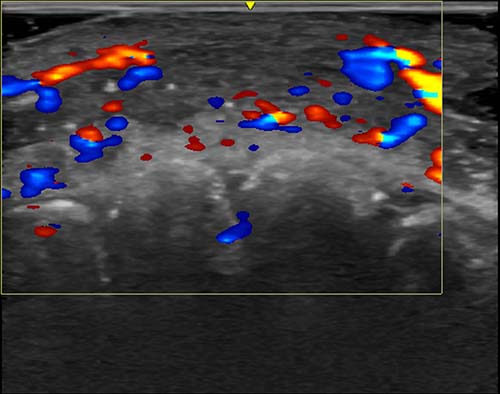

Figure 2. Vascular occlusion—the disruption of blood flow in arteries—on ultrasound from hyaluronic acid fillers. This ultrasound image shows absent blood flow in a segment of an artery of the lip.